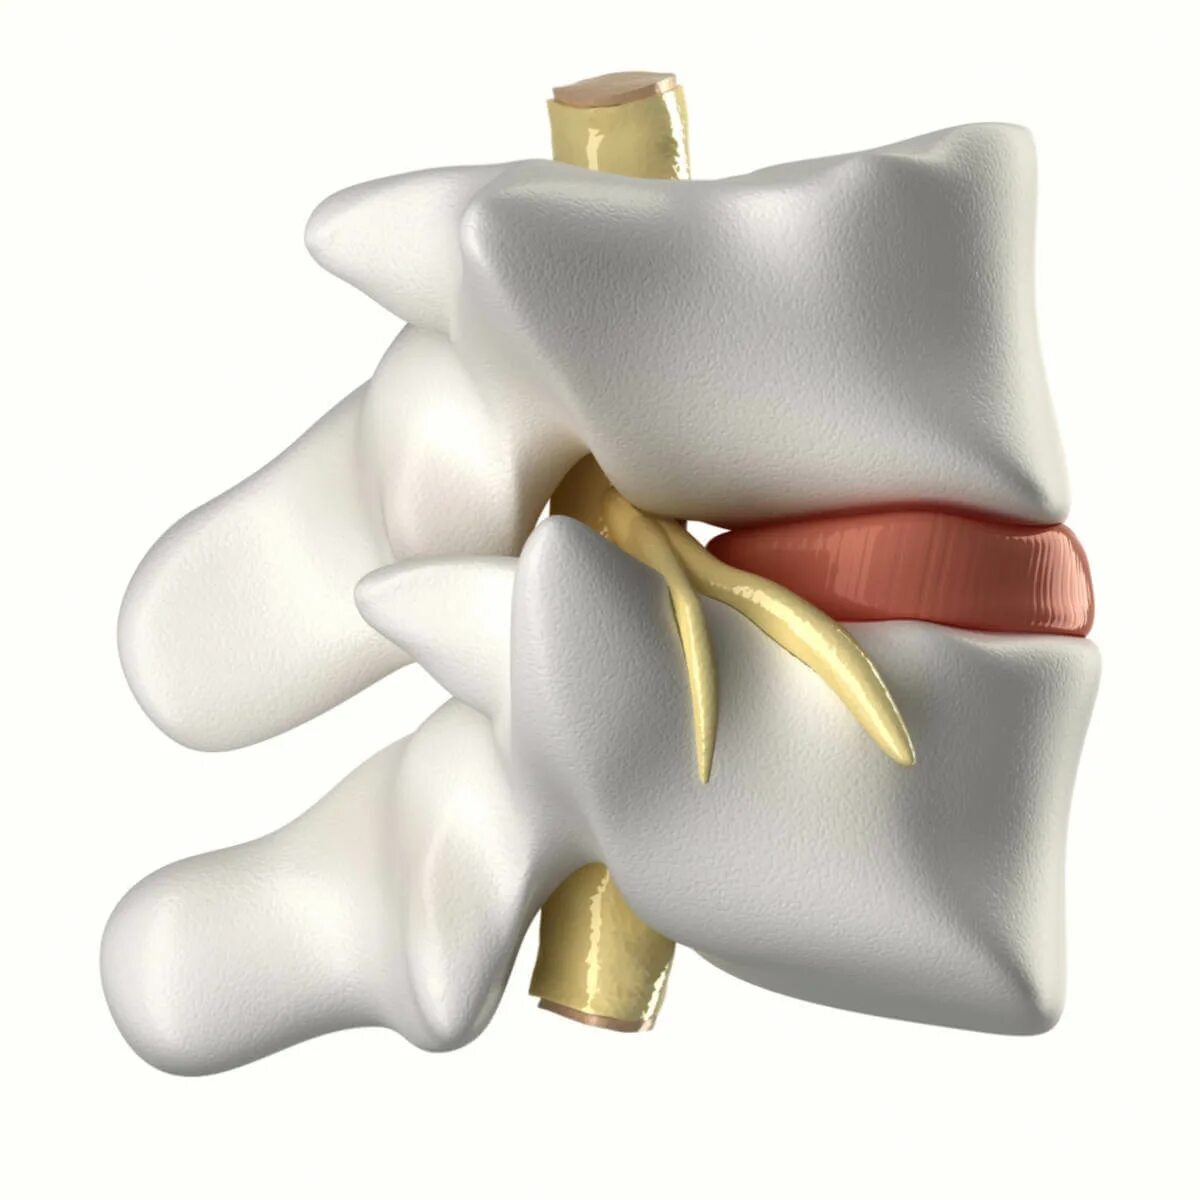

Грыжа шморля позвоночника симптомы и лечение